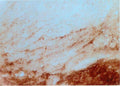

Anti-Beta-synuclein Antibody

Our Anti-Beta-synuclein sheep polyclonal primary antibody detects human and rat Beta-synuclein, and is whole serum. It is validated for use in IHC-Frozen.

IHC: 1:3000-1:8000